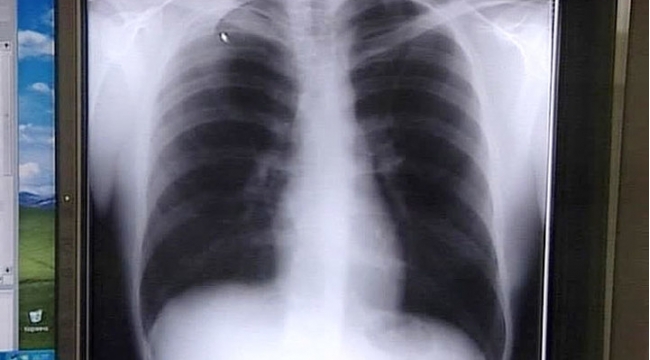

Ağciyər xərçənginin gözlə görünən əlaməti